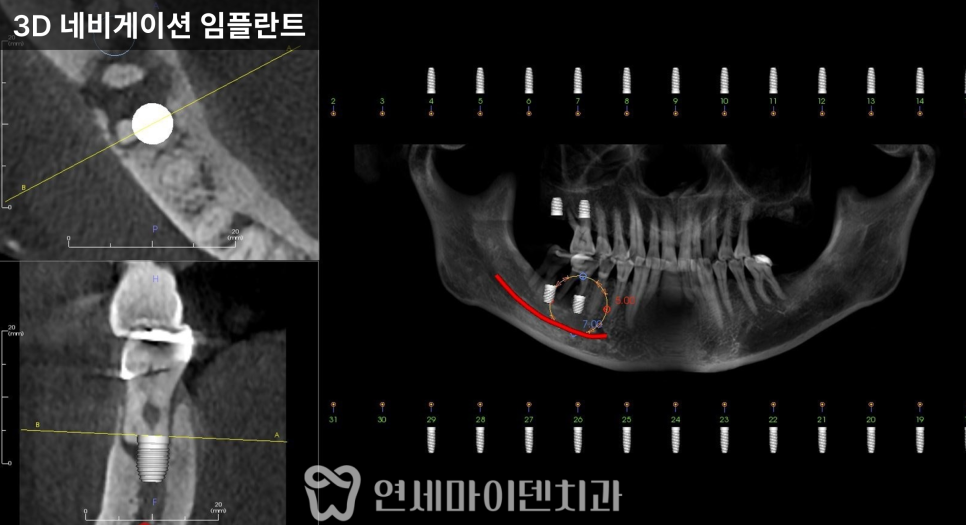

3D 네비게이션 임플란트

또한 아래턱은 하치조 신경관이 지나가는 부위이기 때문에

CT를 통해 정확한 위치를 계획한 뒤

발치와 동시에 임플란트를 식립했습니다.